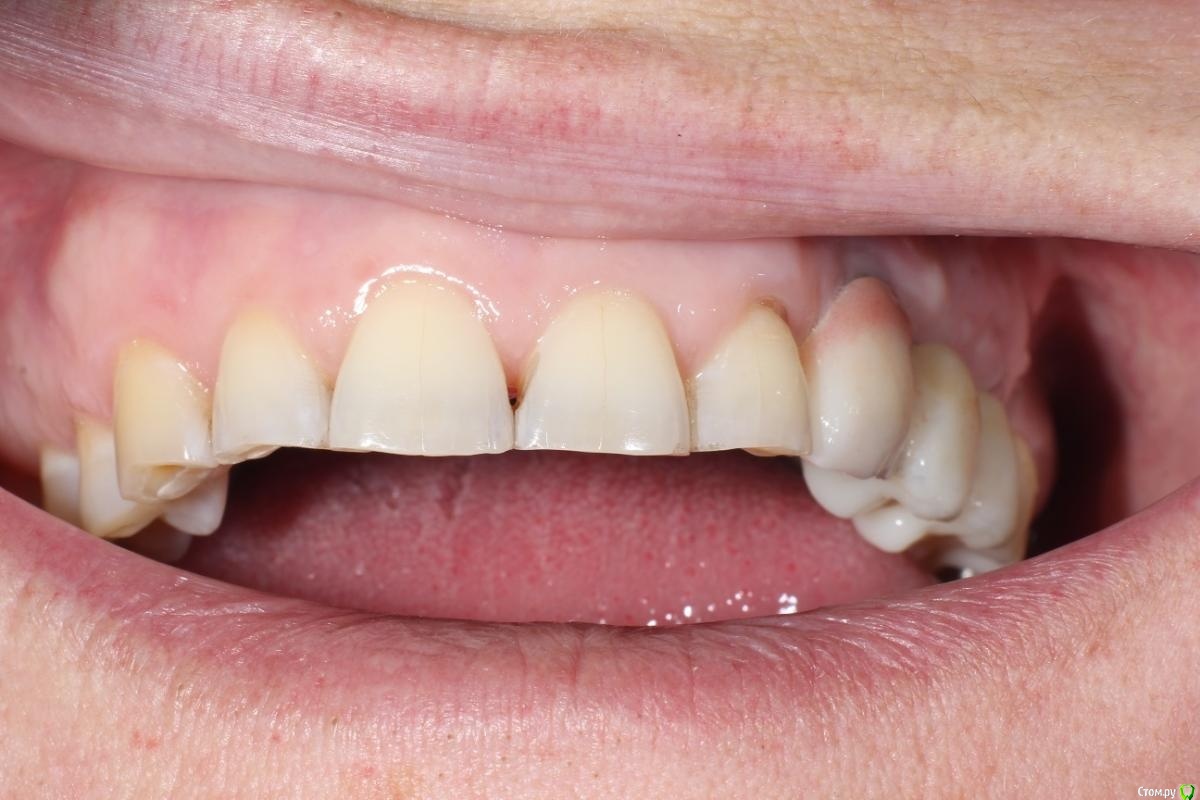

kuziy12 Опубликовано 2 ноября, 2020 Поделиться Опубликовано 2 ноября, 2020 Имплантация с синус лифтингом. Беда с позицией 2.3. Коронки на cad\cam, наносил розовую керамику и красил все сам. Сваливать не на кого) До: После имплантации: Формики: Десна: Постоянная конструкция: Улыбка: 3 Ссылка на комментарий

kuziy12 Опубликовано 9 октября, 2021 Автор Поделиться Опубликовано 9 октября, 2021 Дабы не плодить темы, выложу тут. Докрутил пациента полностью)) Ортопедия тоже моя. От переустановки импланта в области клыка отказалась. Ссылка на комментарий